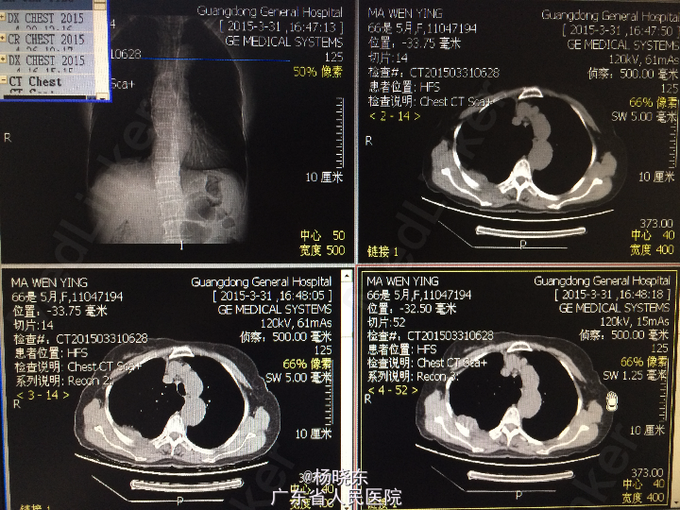

主诉:反复胸背痛1年,加重1月。 病史:患者1年前无明显诱因出现右侧胸背痛,性质为隐痛,无向周围放射。遂至当地医院门诊就诊,查胸部CT,考虑“胸膜肿瘤”,建议手术处理,但患者拒绝未予治疗,症状持续数天后自行消失。后间断出现类似症状,但均可忍耐。1月前患者自觉右上肢上抬及抬举重物时右侧胸背痛明显,不伴有其余部位牵涉痛,未予重视。近1周来,患者自觉症状加重,疼痛致右上肢不可上抬,弯腰时加重,平卧时可缓解。现为进一步手术治疗入院,无发热,无头晕、头痛,无咳嗽、咳痰,无气促、心悸,无恶心、呕吐,无腹痛、腹泻,无皮疹、无双下肢浮肿。自起病以来,精神、睡眠可,食欲可,二便正常,体重近1月下降2kg。

查体:右侧胸肋部及肩胛区压痛明显。 辅查:胸片,CT。

诊断:胸膜间皮瘤 处理:右侧胸膜肿瘤切除术

术中病理显示为结核脓肿,改行右侧胸膜结核性脓肿扩大清除术+右肺楔形切除术。 术后予加用异烟肼+利福平+乙胺丁醇联合抗结核治疗。